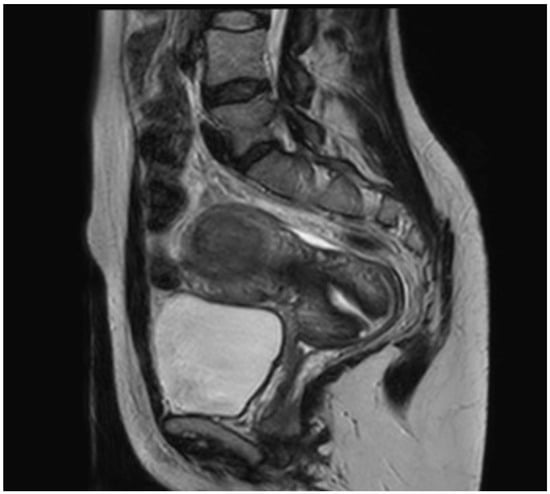

2.2. Case 2